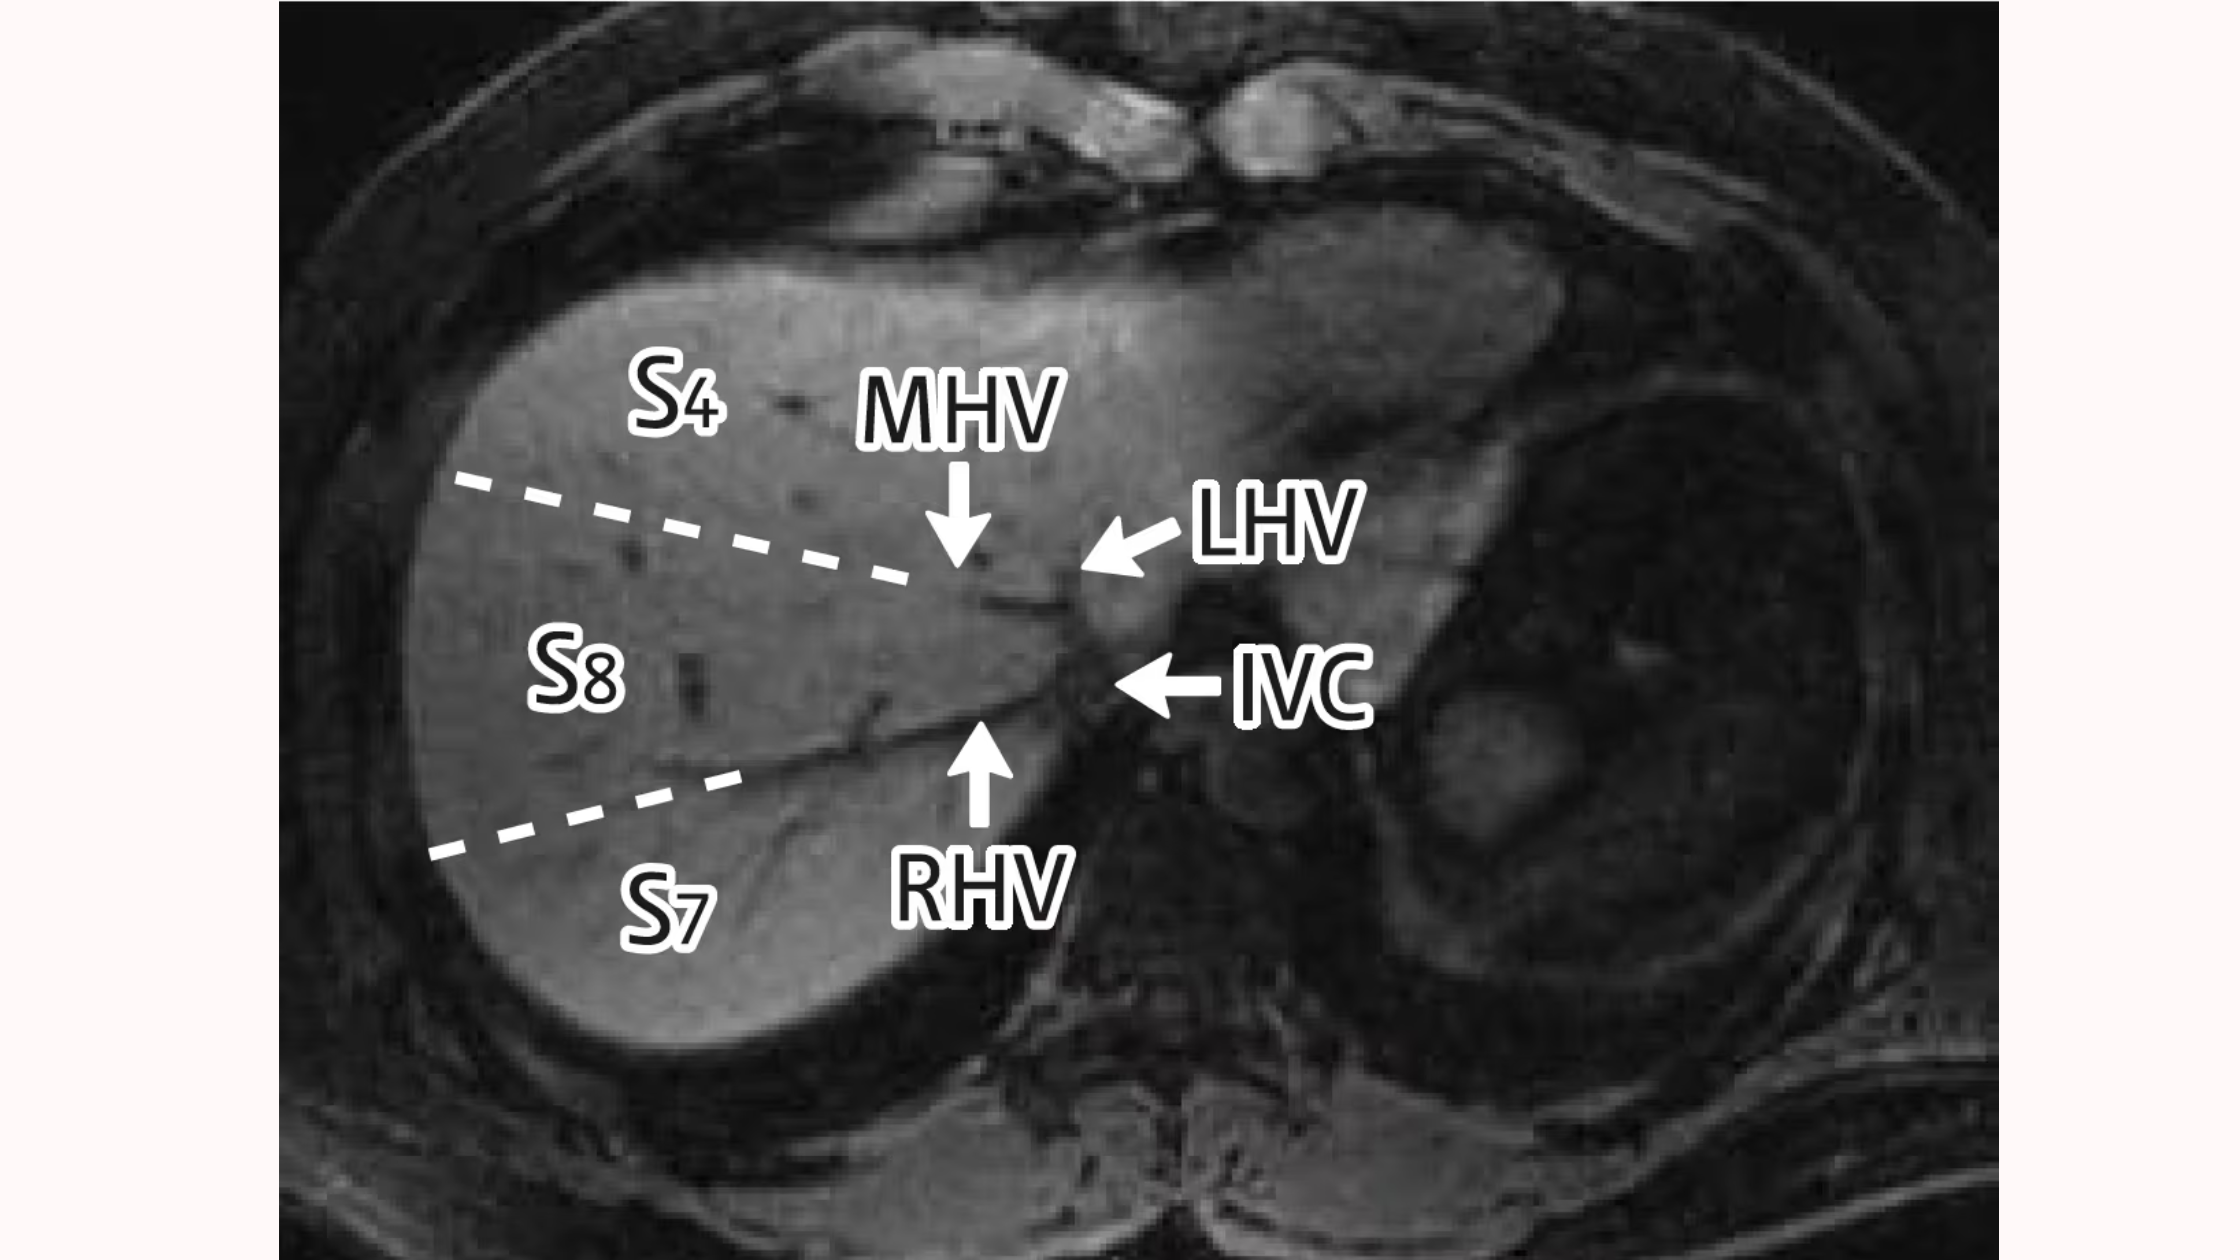

🔢 Couinaud分類(S1〜S8)の特徴を図で理解

肝臓はさらに細かく 8つの区域(S1〜S8) に分けられています。

これが Couinaud分類 です。

| 区域 | 主な位置 | 特徴 |

|---|---|---|

| S1 | 尾状葉 | 独立した血管支配 |

| S2 | 左外側上区域 | 胃・脾臓に近い |

| S3 | 左外側下区域 | 胃に接する |

| S4 | 左内側区域(方形葉を含む) | 肝門部近く |

| S5 | 右前下区域 | 胆嚢に近い |

| S6 | 右後下区域 | 腎臓に近接 |

| S7 | 右後上区域 | 横隔膜に近接 |

| S8 | 右前上区域 | 横隔膜と接する |

👉 区域ごとに「独自の血管・胆管支配」があるため、外科的に切除できる単位になっています。

🖥️ CT断面図で見る肝臓の区域

CT検査では、肝臓を輪切りにした断面像として観察します。

-

右葉と左葉の区別:Cantlie線を意識すると分かりやすい

区域の位置関係:Couinaud分類(S1〜S8)が反映される

臨床での使い方:腫瘍や膿瘍が「どの区域にあるか」を表現するときに必須

👉 たとえば「S6に腫瘍あり」と記録されれば、画像を見た医療者全員が同じ位置をイメージできます。